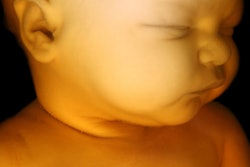

Zou and colleagues wanted to find the link between maternal blood glucose levels and fetal intrauterine growth at different gestational periods. Sonographers measured fetal biometrics using multiple ultrasonographic values (Voluson E8, GE Healthcare).

They looked at data from 3,746 women who had glycemic trajectory data and an average age of 28.6 years. Out of these, 983 women had gestational diabetes.

The study authors found that except for biparietal diameter, fetal biometrics as measured with ultrasound for the women with gestational diabetes or hyperglycemia in all three trimesters were significantly higher. This includes an estimated increase in fetal weight in the group with gestational diabetes (β = 1.82) and in women with hyperglycemia for all three trimesters (β = 1.50; p = 0.002).

Ultrasound also showed fetal biometric alterations among women with gestational diabetes appeared before 24 weeks' gestational age. The birth weight of newborns was on average 40.4 grams heavier than in women without gestational diabetes at 40.4 grams. The risk of large size for gestational age and macrosomia also increased with odds ratios of 1.36 and 1.47, respectively.